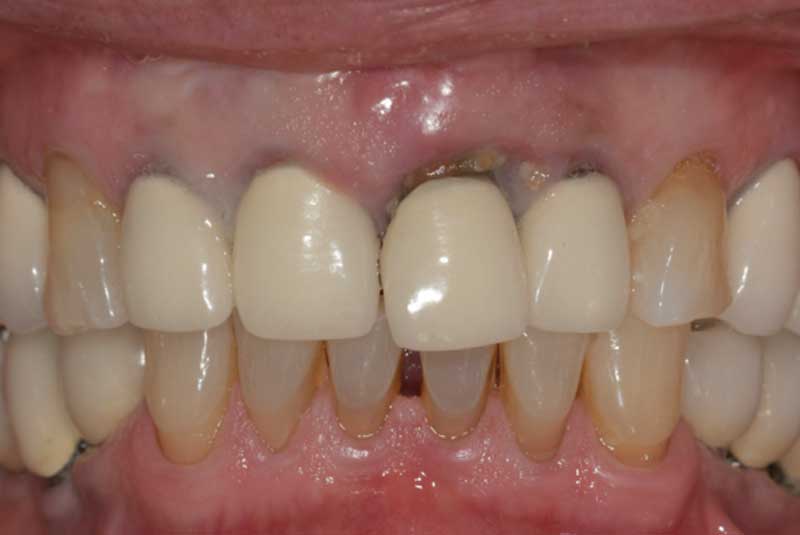

The patient had her implants placed 20 years ago. Four implants, particularly in the maxilla, were not positioned ideally for me to utilize and restore, while the four implants in the mandible were outdated and no longer functional. The patient's primary concern is to restore both function and aesthetics.

Before & After Crowns (#6,7,8,9,10,11,22,23,24,25,26,27), Overlay (#3,4,13,14,21,28,29), Implant & Implant Crowns (#5,12,19,20,30)